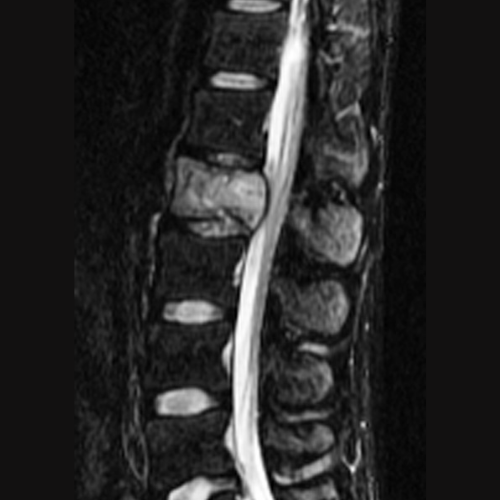

Chiari malformasyonu (yaygın adıyla Chiari sendromu), beyincik (serebellum) dokusunun kafatasının altındaki açıklıktan (foramen magnum) omurilik kanalına doğru sarkmasıyla karakterize yapısal bir bozukluktur. Normal şartlarda tamamen kafatası içerisinde yer alması gereken beyincik parçaları, kafatasının bu bölgedeki hacminin yetersiz olması veya şekil bozukluğu nedeniyle aşağı doğru itilir. Bu durum, hem beyin sapı ve omurilik üzerinde fiziksel bir baskı oluşturur hem de beyin omurilik sıvısının (BOS) doğal akışını engelleyerek merkezi sinir sistemi üzerinde çeşitli baskılara yol açar.

Tedavi süreci, semptomların şiddetine ve hastanın yaşam kalitesine olan etkisine göre planlanır. Ancak şiddetli ağrıların, belirli nörolojik defisitlerin veya sinir sistemi hasarı riskinin bulunduğu durumlarda cerrahi müdahale temel çözüm yoludur. "Posterior fossa dekompresyonu" adı verilen cerrahi işlemle kafatası tabanındaki basınç azaltılır, beyincik için daha fazla alan yaratılır ve beyin omurilik sıvısının normal akışı yeniden sağlanır. Erken teşhis, sinir sisteminde oluşabilecek kalıcı hasarların önlenmesi açısından kritik önem taşır.